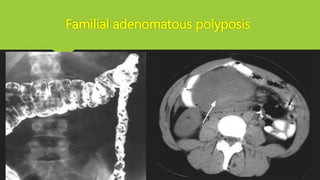

Familial adenomatous polyposis

Gardner syndrome

Turcot syndrome